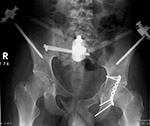

Patient with multiple bilateral pelvic fractures. There is a uniplanar fixator with Schantz pins that transfix both iliac bones with carbon-fiber interconnecting rods (arrows). Two cancellous cannulated screws (proximal fully threaded, distal partially threaded with a washer) transfix the right sacroiliac joint and right sacral fracture. There is a reconstruction plate with four fully threaded cortical screws transfixing the posterior wall of the left acetabulum. From Taljanovic, 2005